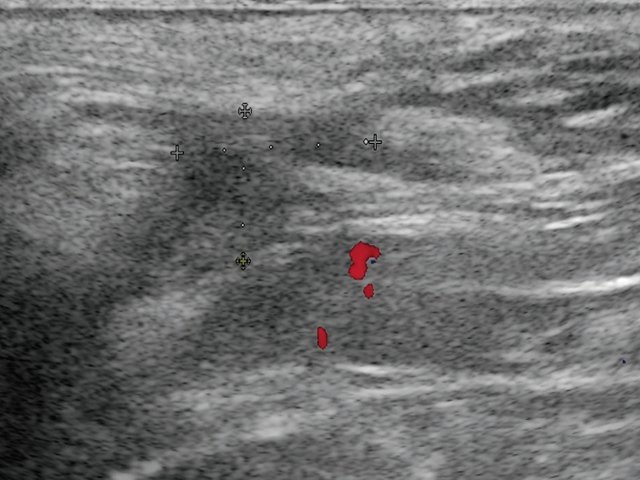

в) Режим ЦДК. В подкожно-жировой клетчатке по периферии образования отмечается обогащение сосудистого рисунка.

в) Режим ЦДК. Через 3 дня после оперативного вмешательства. В подкожно-жировой клетчатке по периферии гипоэхогенного образования отмечается уменьшение степени выраженности сосудистой реакции.